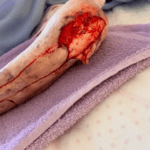

Enrolled Nurse (EN): Permitted Procedures

This page provides a quick reference of Care Plans and Tutorials available on The Wound Sandwich (TWS) which are permitted to be undertaken by staff with a Enrolled Nurse (EN) qualification. Additional applicable qualifications are also listed.